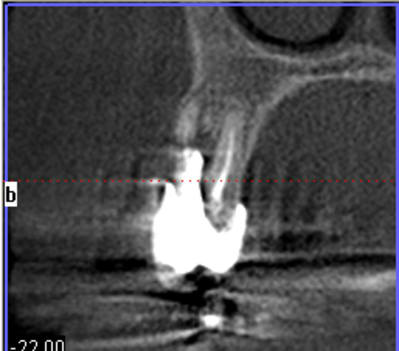

un petit exemple de ce matin: extraction des piliers 12 et 14, curetage, comblement avec du bio-oss de la dépression osseuse vestibulaire au niveau de l'inter 13, comblement des alvéoles 12 et 14 au genos et recouvrement par 2 pédicules conjonctifs. Temporisation avec un partiel amovible.